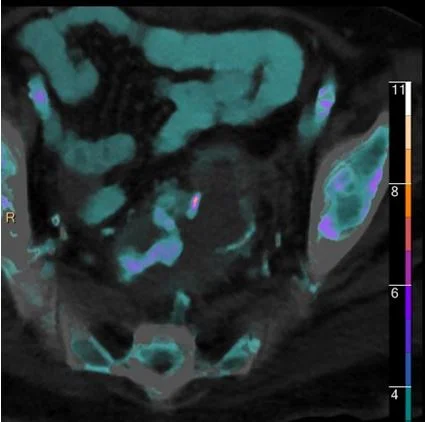

Spectral CT: Like DWI, with CT

Gopal Punjabi

November 9, 2018